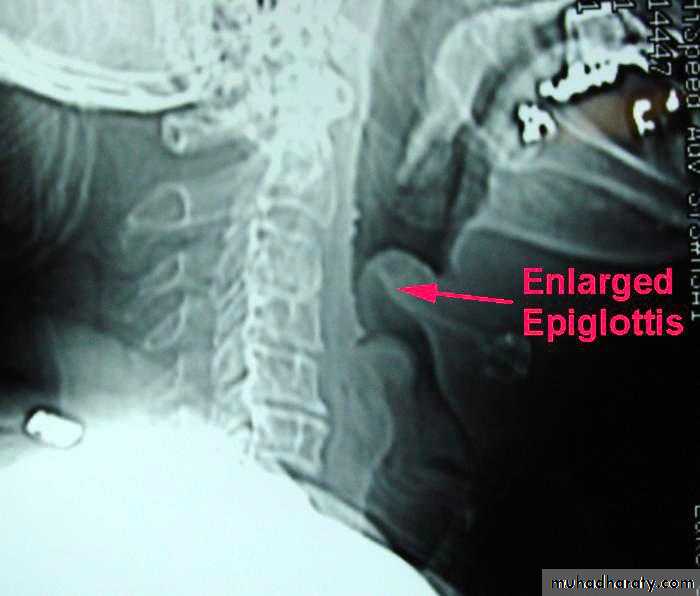

Acute epiglottitis:

Clinical features :Mostly affects young children. Fever and sore throat, progressing to stridor and dysphagia caused by swelling of epiglottis and surrounding structures. Due to H. influenzae type bComplications: Death from asphyxia, which may be precipitated by attempts to examine the throat-avoid using a tongue depressor or any instrument unless facilities for endotracheal intubation or tracheostomy are immediately available

Management: I.v. co-amoxiclav or chloramphenicol therapy essential.Urgent endotracheal intubation or tracheostomy may be necessary